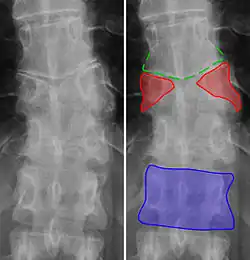

Butterfly vertebra (red). Normal vertebra for comparison (blue). -

Volume rendering of a CT scan of the lumbar vertebral column, showing butterfly vertebrae at several levels, most typically in L1.